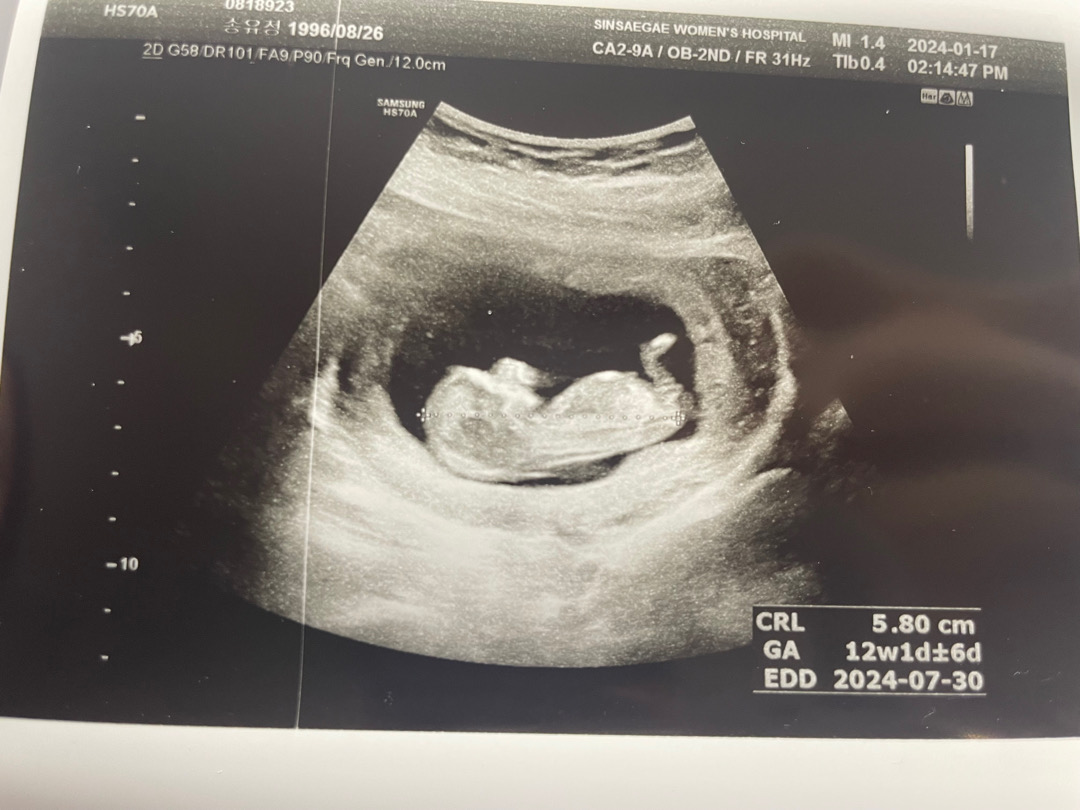

12주0일인데 이 사진으로 각도법 봐주실수있나요ㅎㅎ

저기 배쪽에 튀어나온 게 평평하면 딸이랬는데 딸인 거 같아요! ㅎㅎ